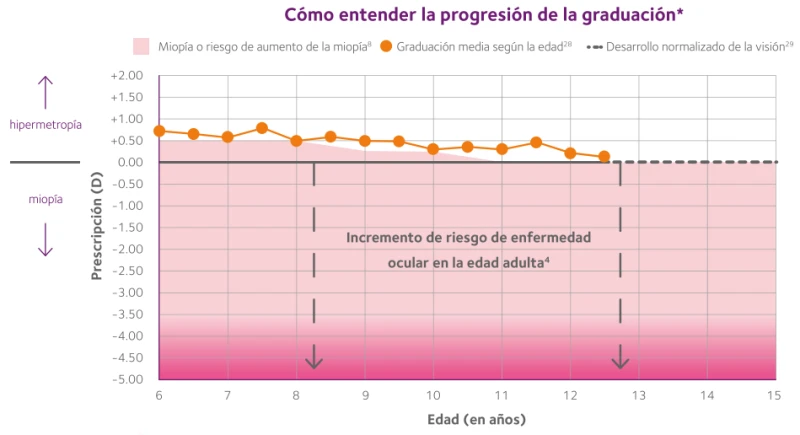

Ahora podemos cambiar las previsiones de la miopía en los niños

Controlar el aumento de la longitud axial y de la graduación en los niños puede ayudar a reducir el riesgo de desarrollar en la edad adulta patologías oculares relacionadas con la miopía, entre ellas:

La graduación corrige lo que ves hoy, pero no frena que la miopía siga aumentando. El control de miopía busca reducir su progresión, especialmente en niños y adolescentes.

Las gafas corrigen, pero no controlan la progresión. El tratamiento va más allá de ver bien, busca proteger la salud visual futura y evitar posibles patologías en el futuro.

La genética influye, pero el entorno también. Hoy existen tratamientos que ayudan a ralentizar la progresión, incluso en niños con antecedentes familiares.

La miopía no suele desaparecer con el crecimiento. De hecho, es en la infancia y adolescencia cuando más rápido puede avanzar.

Precisamente cuando es baja es cuando mejor respuesta tienen los tratamientos. Esperar suele significar perder tiempo valioso.